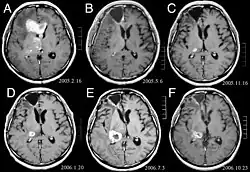

Die Patienten leiden an einer Vielzahl charakteristischer Symptome einer fokalen oder multifokalen massiven Läsion. Das Kernspintomogramm zeigt normalerweise Tumoren mit homogener Kontrastverstärkung innerhalb der tiefen periventrikulären weißen Substanz. Multifokalität und inhomogene Verstärkung sind typisch für Patienten mit geschwächtem Immunsystem. Extrem wichtig ist die Analyse des ZNS-Lymphoms bei der Differentialdiagnose von Hirnneoplasien. Es sollte beachtet werden, dass die Verabreichung von Kortikosteroiden zum vollständigen Verschwinden der Verstärkung führen kann, was Diagnose der Läsionen erschwert. Wenn das ZNS-Lymphom in der Differentialdiagnose berücksichtigt werden soll, sollten folglich Kortikosteroide vermieden werden, es sei denn, der Masseneffekt verursacht ein ernstes und unmittelbares Problem beim Patienten.

Früher wurde das gesamte Gehirn (panenzephal) einer Strahlentherapie unterzogen. Dabei beträgt das mediane Überleben selbst bei lokalisierten Läsionen etwa 12 Monate. Das Wiederauftreten betrifft normalerweise den Ort der vorherigen Verletzung sowie andere Regionen. Die Reaktionen auf eine Chemotherapie sind vielversprechender. Klinische Studien, in denen hochdosiertes Methotrexat allein als erste Behandlung angewendet und die Strahlentherapie auf den Zeitpunkt des Rückfalls oder Fortschreitens verschoben wurde, zeigten ein besseres Gesamtüberleben als die Strahlentherapie allein. Noch effektiver war die Kombination von Methotrexat, Vincristin, Procarbazin, intrathekalem Methotrexat, Cytarabin und panenzephaler Strahlentherapie und Cytarabin bzw. die Anwendung einer intraarteriellen Chemotherapie mit intraarteriell verabreichtem Methotrexat, intravenös injiziertem Cyclophosphamid und Etoposid nach Modifikation der Blut-Hirn-Schranke mit Mannit. Das mediane Überleben in Methotrexat-Therapien war mit 24 bis 40 Monaten viel höher als bei alleiniger Strahlentherapie (Bereich 24 bis 40 Monate). In einigen Fällen wird die Strahlentherapie nur bei Rückfällen angewendet, wenn bei einer Chemotherapie eine anfängliche Regression auftritt. Fälle von langem Überleben wurden auch ohne Strahlentherapie berichtet.[41][42][43]

Bei Diagnose und Behandlung dieser Läsionen wurden in jüngster Zeit erhebliche Fortschritte erzielt, wodurch das Überleben und die Kontrolle der Symptomatik verbessert wurden. Das Auftreten von Anzeichen und Symptomen ähnelt denen anderer massiver Läsionen im Gehirn. Das Diagnoseverfahren der Wahl ist die Kernspintomographie unter Verwendung von Kontrastmitteln.